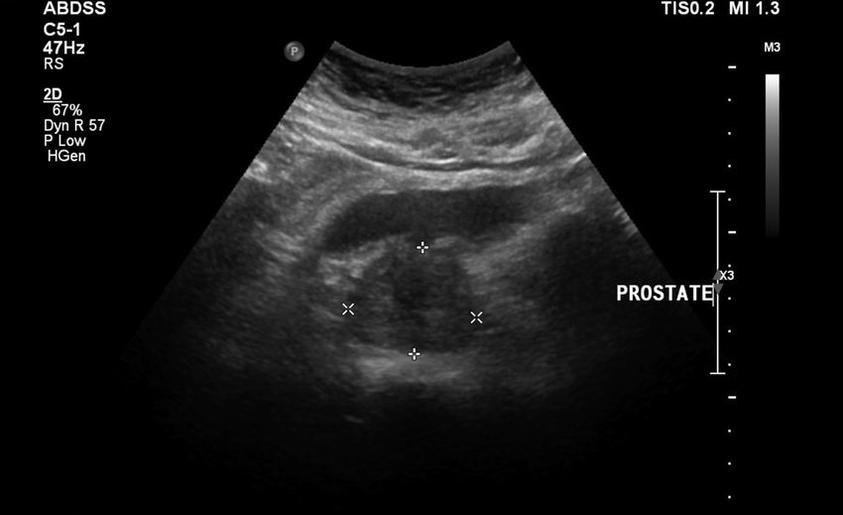

Nedovolili, aby bol gumberizovaný pokoj pokojne, potom sa pridala bolesť dolnej časti chrbta, testy a výsledky ultrazvuku boli zlé. Doslova bolo nemožné odísť z toalety, v slabinách a neustálej bolesti bol pocit ťažkosti. Priama masáž prostaty bola predpísaná, ktorá ma ponorila do paniky. Začal hľadať ďalšie, menej traumatické metódy liečby.